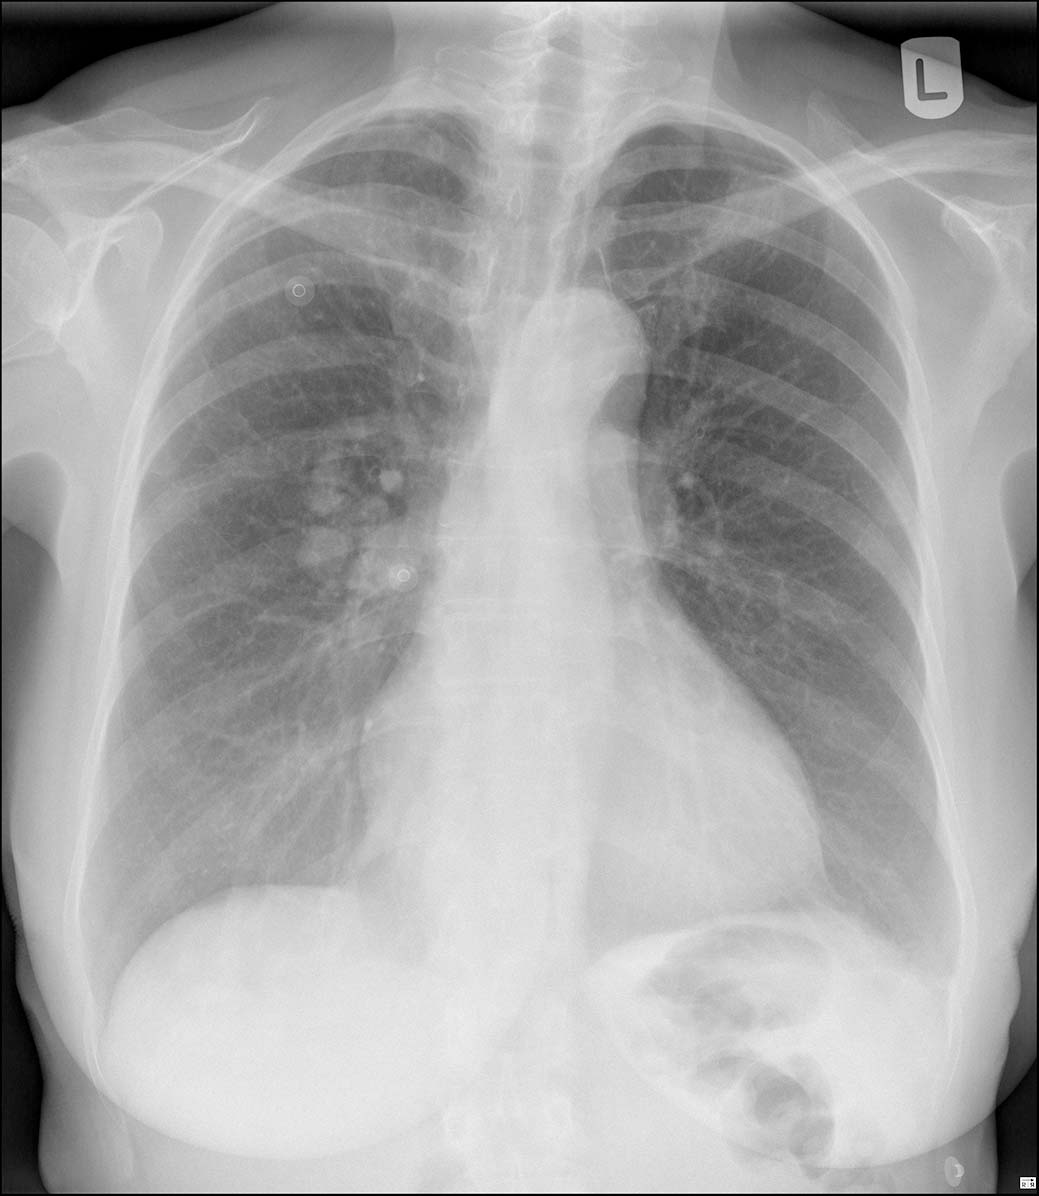

Een verrassende oorzaak van dyspneu: Rendu-Osler-Weber

Er komt een patiënte op het spreekuur die last heeft van inspanningsdyspneu en pijn op de borst. De huisarts denkt aan een cardiale oorzaak. Toch is er iets anders aan de hand, want er zijn klinische aanwijzingen voor een zeldzame aandoening: de ziekte van Rendu-Osler-Weber. Waar moet u op letten?